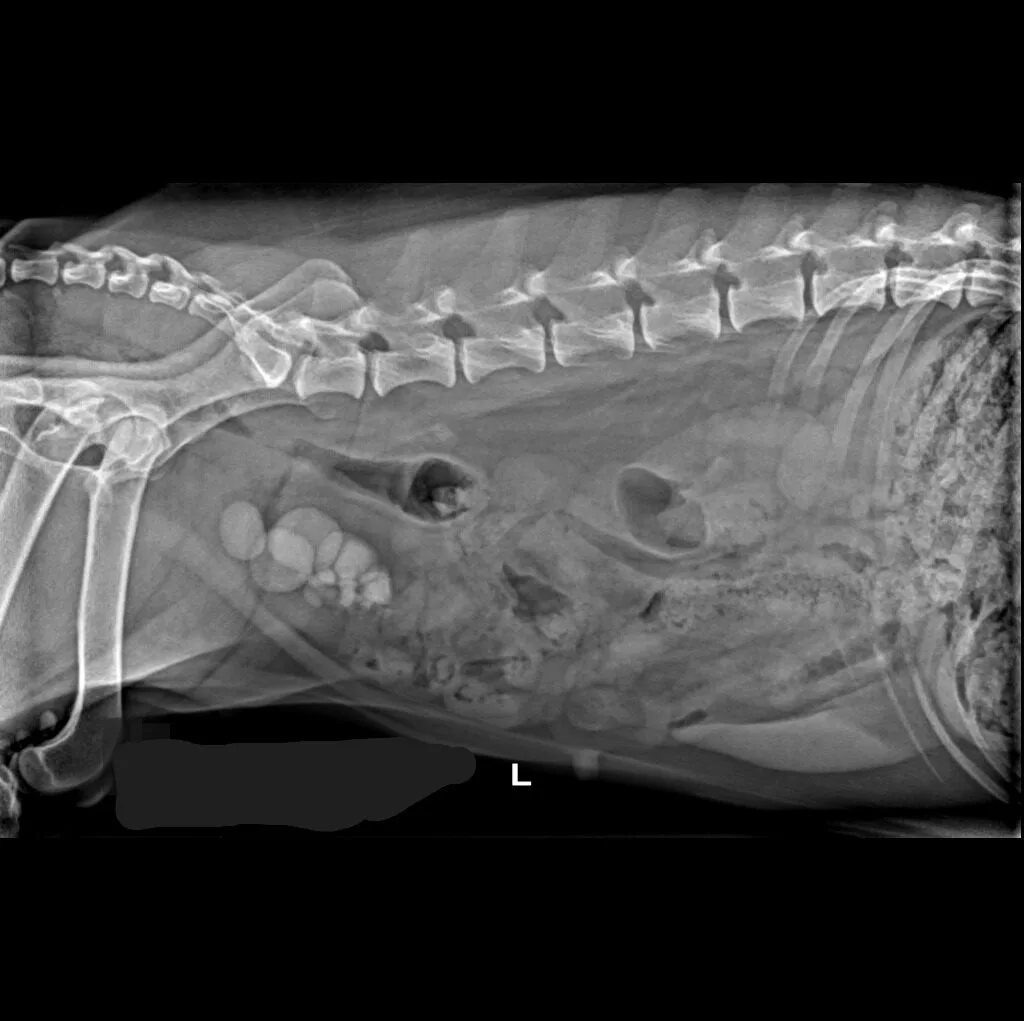

🔹 Lameness & Joint Issues – Identifying fractures, arthritis, and mobility concerns

🔹 Abdominal & Gastrointestinal Issues – Detecting obstructions, tumors, or organ abnormalities

🔹 Cancer Screening – Locating tumors and assessing disease progression